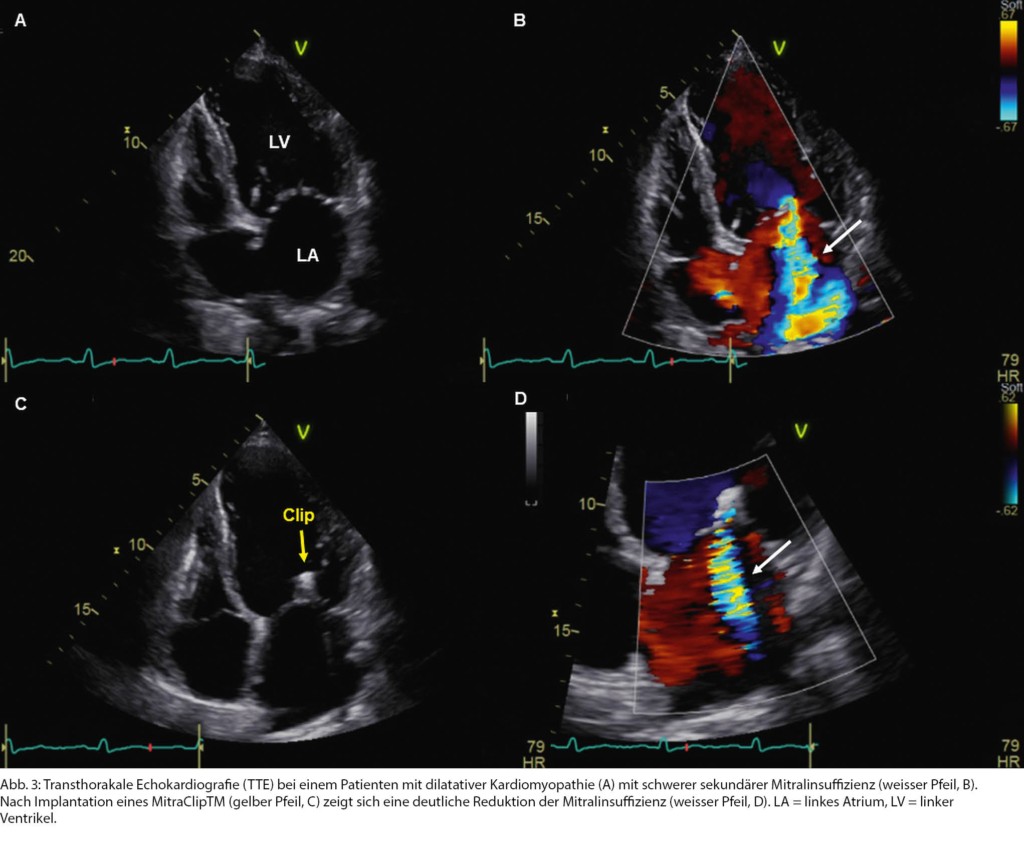

Dies traf auf einen 66-jährigen Patienten zu, bei dem eine dilatative Kardiomyopathie bekannt war. In letzter Zeit beklagte er eine zunehmende Leistungsintoleranz. Bei dilatiertem LV mit schwer eingeschränkter LVEF fand sich neu eine schwere sekundäre MI (Abb. 3 A, B). Bei hypotonen Blutdruckwerten mit Schwindelsymptomatik liess sich die medikamentöse Herzinsuffizienztherapie nicht weiter ausbauen. Da angiografisch keine behandlungsbedürftige koronare Herzkrankheit vorlag, wurde der Patient in Hinblick auf eine TEER abgeklärt (Tab. 1). In der TEE waren die anatomischen Verhältnisse hierfür geeignet. Die TEER mittels eines MitraClipTM konnte in der Folge erfolgreich durchgeführt werden, was zu einer deutlichen Reduktion der Mitralinsuffizienz führte (Abb. 3 C, D).